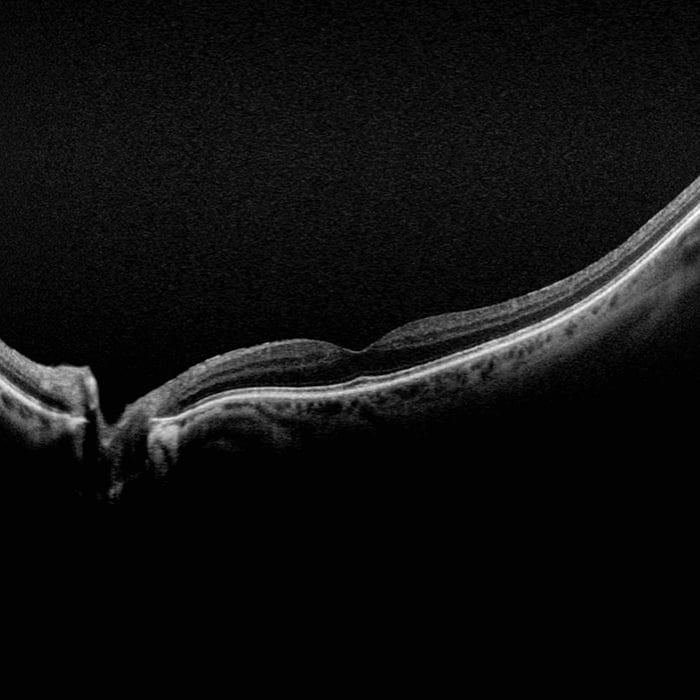

Optical Coherence Technology (OCT) uses light waves to take cross-section pictures of your retina. With OCT, you can see each of the retina’s distinctive layers. This allows you to map and measure their thickness which will assist in diagnosis and provide treatment guidance for retinal diseases such as, but not limited to; glaucoma, diabetic eye disease, and AMD. These measurements help with diagnosis.